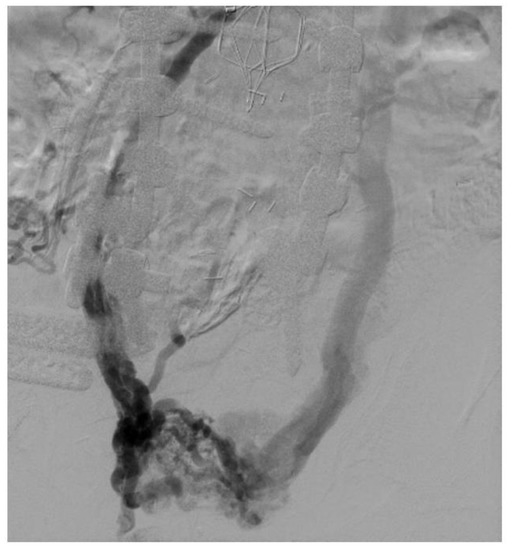

Glissonean Pedicle Isolation Focusing on the Laennec’s Capsule for Minimally Invasive Anatomical Liver Resection

Cited by 12 | Viewed by 5478

Background: Inflow control is one of the most important procedures during anatomical liver resection (ALR), and Glissonean pedicle isolation (GPI) is one of the most efficacious methods used in laparoscopic anatomical liver resection (LALR). Recognition of the Laennec’s capsule covering the liver parenchyma [...] Read more.